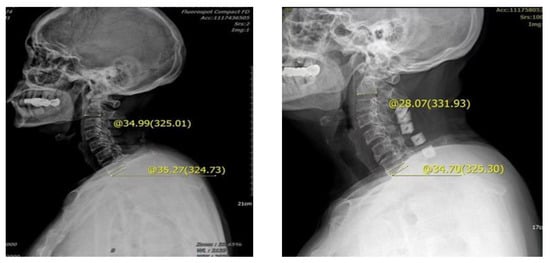

Figure 4.

Male, 62 years old, preoperative diagnosis: CSM, cervical vertebra 3–7 posterior double door. The preoperative tilt angle of T1 was 35.27°, the preoperative cervical curvature was 34.99°, the postoperative follow-up was 3 months, the cervical curvature was 28.07°, and the cervical curvature lost 6.92°.